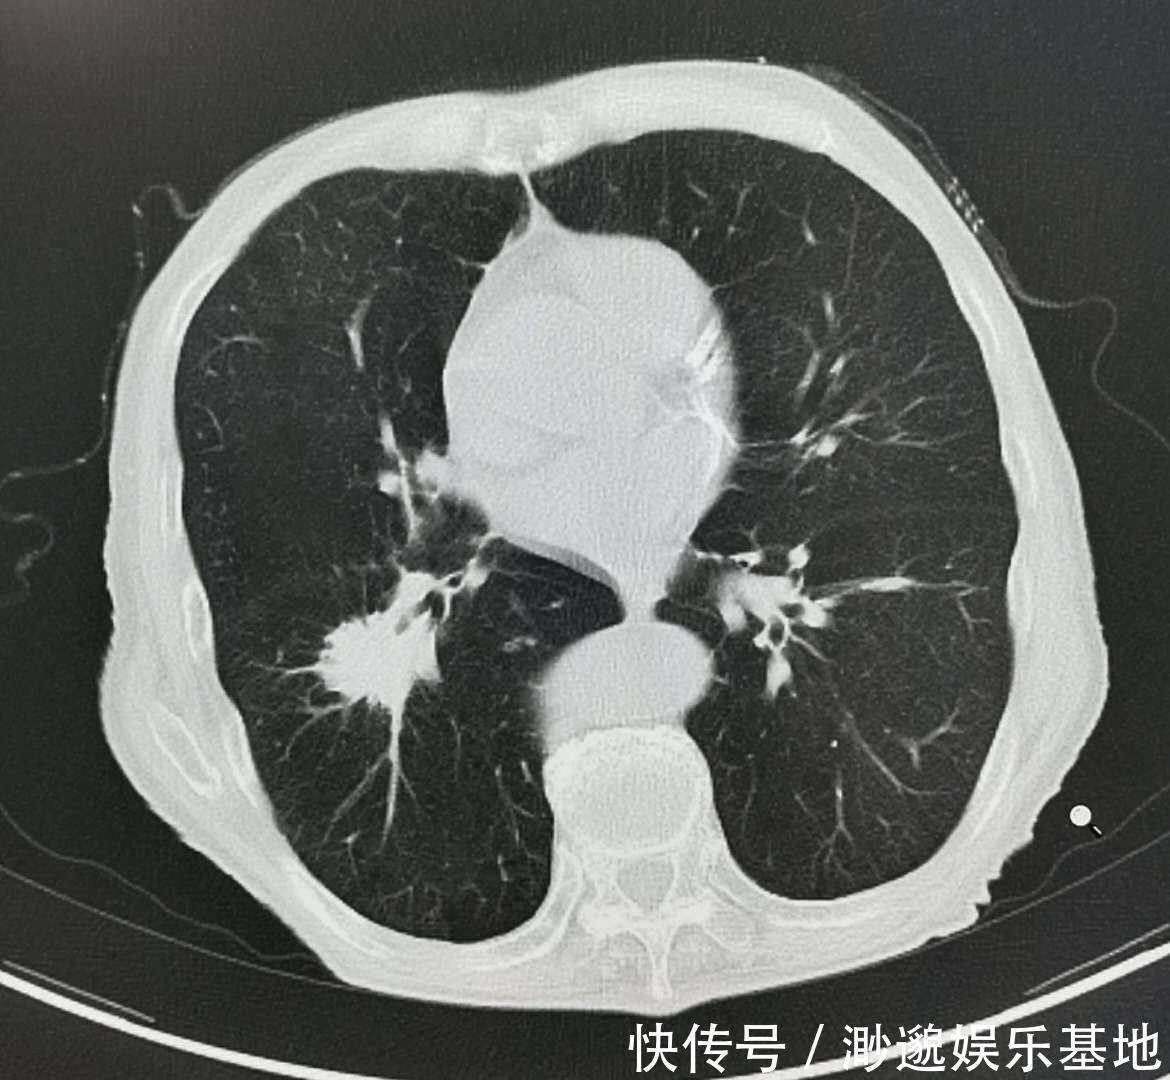

有人说:“癌症根本治不好,治好的都是误诊!”还别说,持这个观点的人真不少。如果癌症都治不好,地球上所有的肿瘤医院都关停吧,这是小看天下英雄了!稍微留意一下就能发现,早在三四十年前,胃癌、乳腺癌就能治愈了。所有的癌症都能治愈吗?这个确实不能!每个时代的医学都有局限性,古时候伤寒、疟疾、结核都是致命性疾病,甚至一场感冒也能夺去很多人的性命,人均寿命低,儿童早夭的很多。到了21世纪的今天,心血管疾病和恶性肿瘤成为限制人类寿命的两大主因。但也应该认识到,早期癌症并不可怕,早期可以治愈,可怕的是晚期癌症。而肿瘤治疗学的研究使命,就是追求治愈所有的早期癌症,争取延长中晚期癌症病人的生存期。令人欣慰的是,晚期癌症病人的生存期一直在提升,癌症5年生存率也一直在提升。据复旦大学附属中山医院白春学教授介绍:“在经过综合治疗后,肺癌患者的5年存活率从20年前的8%上升到了现在的19.7%,而晚期肺癌患者的生存期也从过去的10个月延长到现在的两年左右。这里是文章图片\1.png像这位老人,胸闷发现左肺尖占位,活检病理为大细胞神经内分泌癌,首次发现时就已经有肺门和纵隔淋巴结转移,不能手术了,但经过放化疗为主的综合治疗,已经5年多了,至今健在!